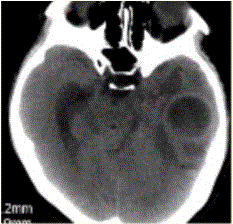

问题 患者女,26岁,头痛、低热10d余,既往有左侧慢性中耳炎病史。CT表现如下图。 脑脓肿的MRS表现,正确的是

选项 A.Cho明显升高 B.NAA未见异常 C.Lac升高 D.乙酸峰、乳酸峰、丁二酸峰升高 E.Lip峰升高

答案 D